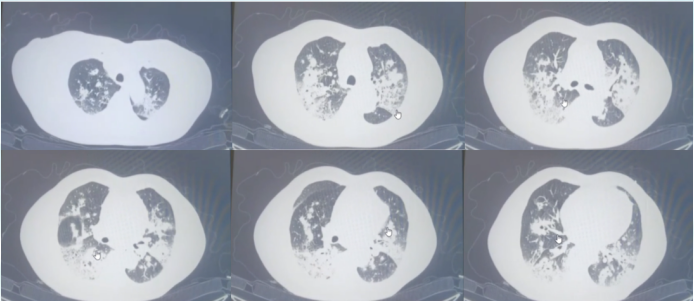

7. 复发

2022年9月24日(出院约10天):患者突发高热、胸闷、气喘加重再次入院。查血常规:Hb 104 g/L,WBC 1.94×109/L,NEU 0.05×109/L,PLT 381×109/L;血气分析:pH 7.450,PaO2 81.1 mmHg,PaCO2 28.4 mmHg,血浆中碳酸氢盐浓度19.3 mmol/L,Glu 7.6 mmol/L,Lac 1.5 mmol/L。9月26日胸部CT:两肺多发感染,特异性感染不除外,较前片(2022-09-12)部分病灶范围稍缩小,部分病灶内空洞缩小,余变化不明显9;肺气肿,慢性支气管炎;纵隔内多发肿大淋巴结,较前大致相仿;心影增大;心包少许积液,较前新增,两侧胸膜增厚。

图片

9  患者再次入院胸部CT(2022-09-26)

8. 再次治疗与长期管理

调整方案(2022年9月底):考虑伏立康唑(集采药)及雾化治疗可能未能完全清除真菌或存在突破感染。予两性霉素B胆固醇硫酸酯复合物(ABCD)静脉治疗。10月8日复查胸部CT,病变较9月26日进一步吸收(图10)

10  复查胸部CT(2022-10-08)